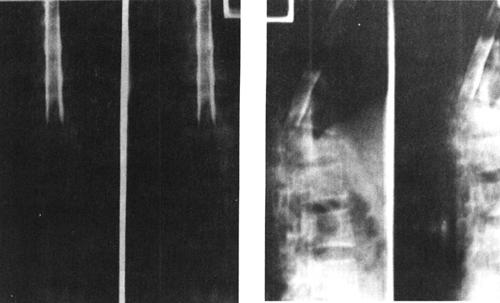

图7-17 T12压缩性骨折并脊髓横断性损伤:T1W(a)和T2W(b)矢状面扫描,可见T1压缩变扁,T11以上向前移位,脊髓呈横断性改变。椎间盘及脊柱前纵韧带下血肿。冠状面脊柱两侧亦见高信号出血

(5)脊髓横断:脊髓横断表现为脊髓和硬膜囊连续性中断,在矢状面显示清楚。完全性横断可伴有脊髓的回缩,两断端出现较宽的间隙。MRI检查T2WI较T1WI敏感,可清楚显示横断的脊髓,尤其是在T2WI,脑脊液呈高信号,而脊髓呈中等信号,两断端间充满高信号的脑脊液(图7-18)。不完全性脊髓横断,在T2W呈高信号,脊髓连续性尚存。

图7-18 T11椎体骨折脱位伴脊髓横断性损伤:T1W(a)和T2Wb矢状面示,T10以上明显向前脱位,椎管和脊髓在T11水平中断和成角,脊椎前、中、后柱骨折脱位,并有脊柱周围血肿